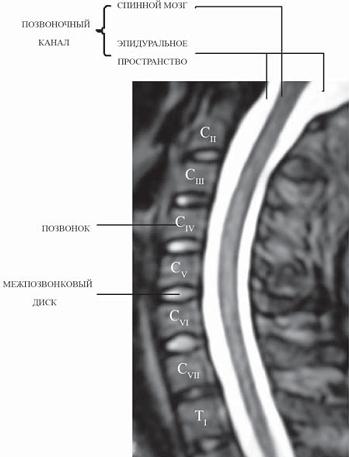

МРТ № 2

На МРТ № 2 — грудной отдел в состоянии «норма»

Грудной отдел должен иметь нормальную степень кифоза (угол кифоза по Stagnara формируется линией, параллельной замыкательным пластинкам ТIII и ТXI= 25°). Позвоночный канал на грудном уровне имеет округлую форму, что делает эпидуральное пространство узким почти по всей окружности дурального мешка (0,2–0,4 см), а на участке между TVI и ТIX он наиболее узок. Сагиттальный размер: ТIХI = 13–14 мм, ТXII = 15 мм. Поперечный диаметр: > 20–21 мм.

Высота межпозвонковых дисков: самая меньшая на уровне ТI, на уровне ТVIХI приблизительно 4–5 мм, наибольшая на уровне ТХIХII.